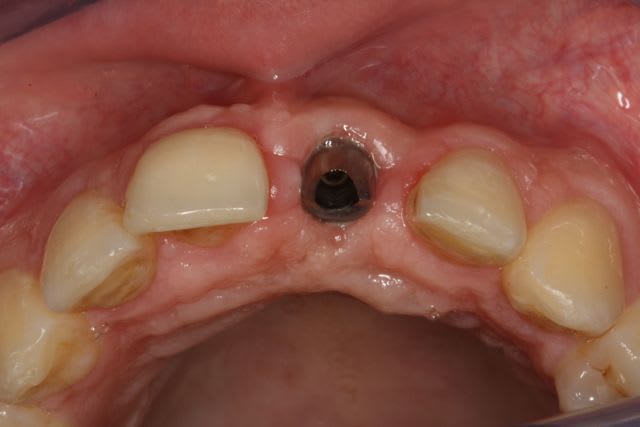

greffe onaly,

dépose des vis et pose de l'implant à 5mois1/2 avec un cj roulé et mise en place de la vis de cica,

et 3 mois 1/2 après empreinte

15j après essayage pilier et biscuit, visite au labo pour "finition en bouche" et 3 h après scellement.

nobel effectivement: RP Replace Groovy 4*13

Non pas speedy mais straight: apex moins agressif et implant moins compressif

J'ai eu beaucoup de craterisation avec le speedy ( surtout sur des sites anciens ) et sur une greffe je préfère la mise en place plus douce du straight pour ne pas risquer de 'décoller' le greffon cortical